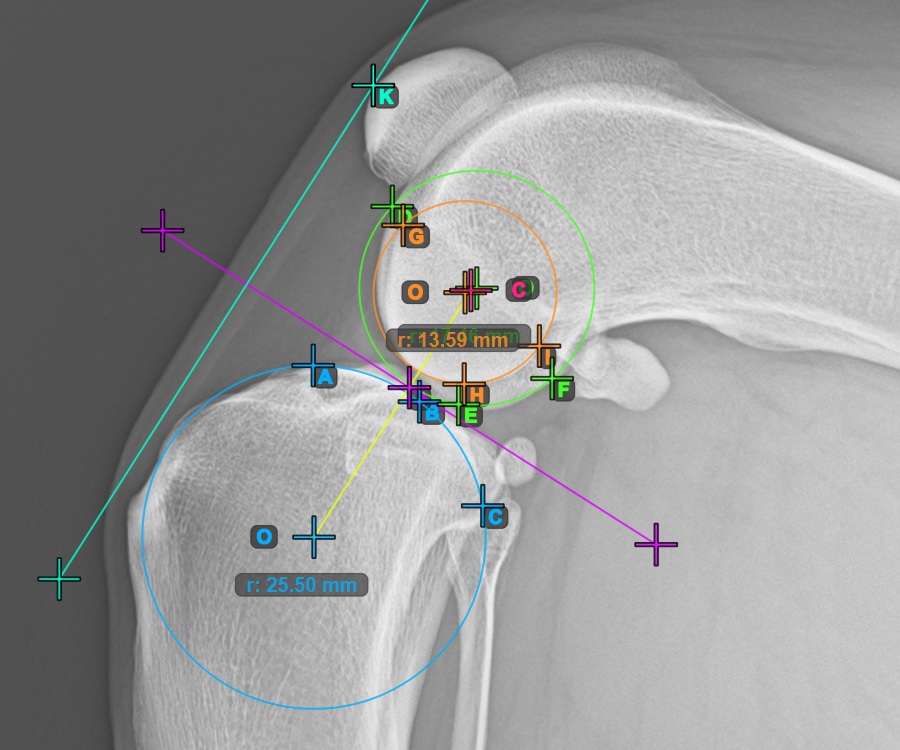

Fahren Sie fort, indem Sie die drei Punkte auf der Gelenkfläche des ersten Condylus Femoris markieren.

Markieren Sie die drei Punkte am Hauptkondylus des Oberschenkelknochens (Condylus Femoris). Unabhängig von der Reihenfolge stellen Sie sicher, dass Sie den vordersten Punkt, den hintersten Punkt und den Mittelpunkt des Condylus Femoris markieren. Basierend auf den drei gesetzten Punkten wird automatisch ein Kreis konstruiert.

Das Bild unten zeigt die typische Platzierung der drei Punkte am ersten Condylus Femoris.